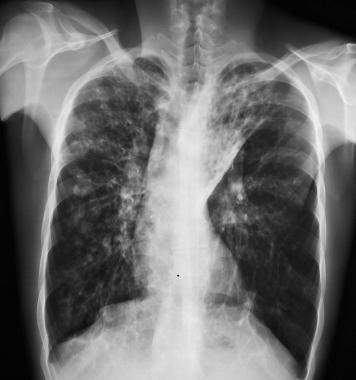

图3 囊性纤维化患者双侧支气管扩张 , 并伴有左上叶肺不张

图4 右肺完全不张伴支气管扩张 , 注意左肺过度充气

图5 27岁患者仅有轻微症状 , 显示为支气管壁增厚、双侧小结节状浑浊和脊柱侧弯 。